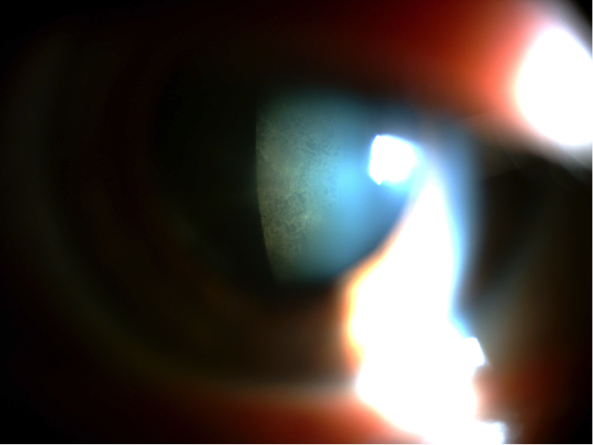

Alguna de las circunstancias que pueden hacer la cirugía más laboriosa es la insuficiente dilatación de la pupila o el cierre de la misma durante la intervención, más frecuente en pacientes que toman tratamientos para la hiperplasia benigna de próstata, que con frecuencia afectan al iris, causando lo que se denomina Sindrome de Iris Flacido. En el siguiente video, podemos ver el ejemplo del segundo ojo de un caso así, donde directamente, por la experiencia vivida en el otro ojo, dilatamos la pupila mecánicamente con retractores de iris en previsión de posibles complicaciones, completando la cirugía sin incidencias.